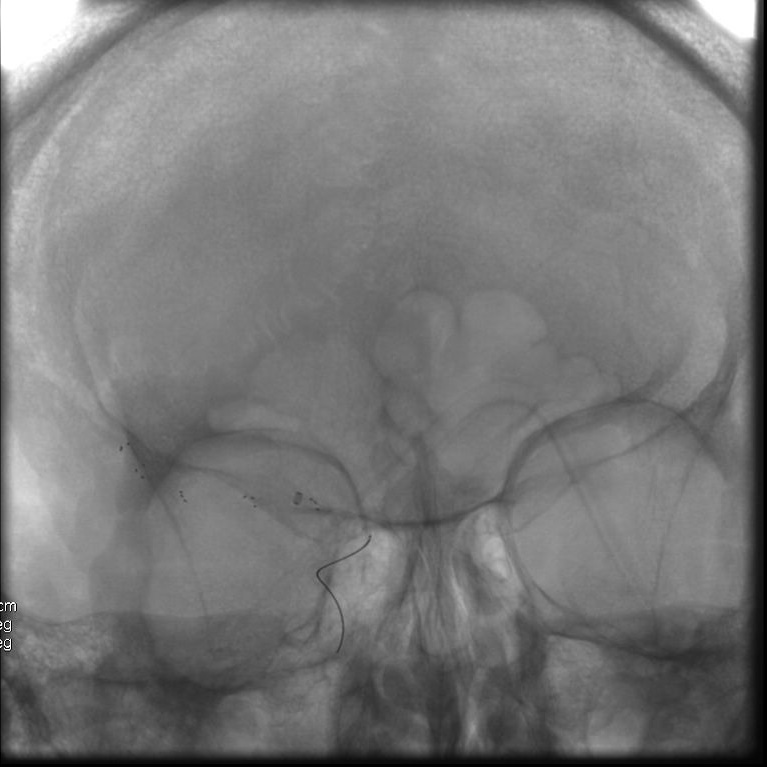

Patient présentant un AVCAccident Vasculaire cérébral : un déficit neurologique soudain d'origine vasculaire causé par un infarctus ou une hémorragie au niveau du cerveau https://fr.wikipedia.org/wiki/Accident_vasculaire_cérébral More ischémique aigue droit en rapport avec une occlusion proximale de l’artère cérébrale moyenne. Thrombolyseconsiste à lyser (désagréger) par médicament les thrombus (caillots sanguins) obstruant les vaisseaux sanguins https://fr.wikipedia.org/wiki/Thrombolyse More intraveineuse puis thrombectomieretrait mécanique d'un thrombus (synonyme de caillot sanguin) dans un vaisseau sanguin, veine ou artère https://fr.wikipedia.org/wiki/Thrombectomie More par voie endovasculaire retrouvant cette occlusion proximale. Reperfusion rapide permettant de limiter l’extension de l’AVCAccident Vasculaire cérébral : un déficit neurologique soudain d'origine vasculaire causé par un infarctus ou une hémorragie au niveau du cerveau https://fr.wikipedia.org/wiki/Accident_vasculaire_cérébral More ischémique et les séquelles neurologiques.